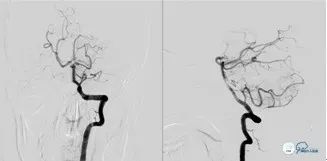

入院时急查头颅CT示:颅脑未见明显异常。ASPECT评分10分。

入院时急诊头颅CT:

图1